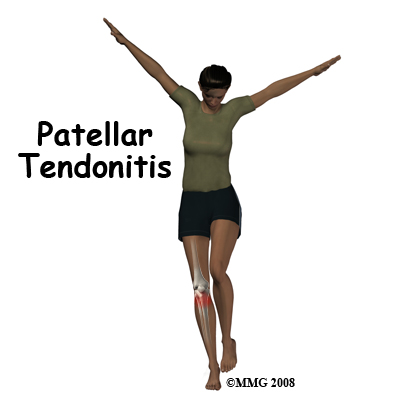

Welcome to FYZICAL Havertown's patient resource about Patellar Tendonitis.

Alignment or overuse problems of the knee structures can lead to strain, irritation, and/or injury. This produces pain, weakness, and swelling of the knee joint. Patellar tendonitis (also known as jumper's knee) is a common overuse condition associated with running, repeated jumping and landing, and kicking.

Pain from patellar tendonitis is felt just below the patella. The pain is most noticeable when you move your knee or try to kneel. The more you move your knee, the more tenderness develops in the area of the tendon attachment below the kneecap.

There may be swelling in and around the patellar tendon. It may be tender or very sensitive to touch. You may feel a sense of warmth or burning pain. The pain can be mild or in some cases the pain can be severe enough to keep the runner from running or other athletes from participating in their sport. The pain is worse when rising from a deep squat position. Resisted quadriceps contraction with the knee straight also aggravates the condition.